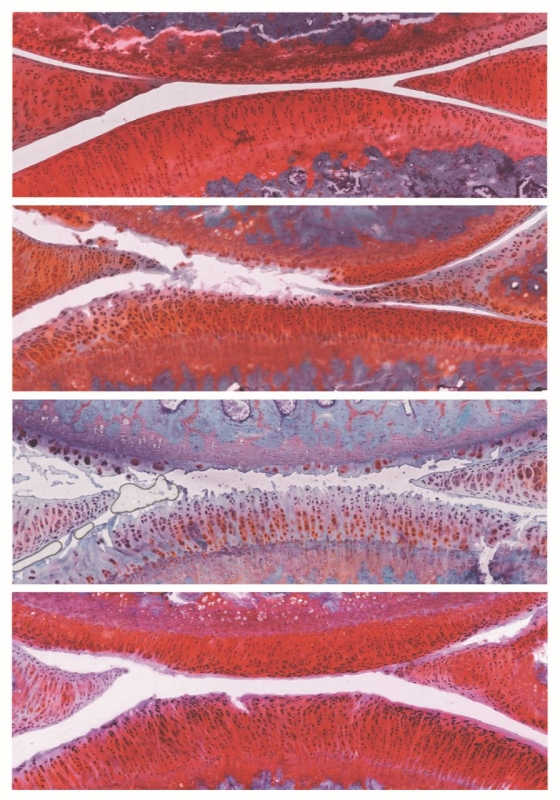

Pasadas seis semanas, las ratas tratadas mostraron una recuperación: su cartílago era más grueso, morían menos células y, además, proliferaban activamente. La enfermedad mejoró de la etapa 2 a la 1, una forma leve de osteoartritis, y no se observaron efectos secundarios adversos.

Los experimentos revelaron que, en las células de cartílago de ratas tratadas, 136 genes eran más activos y 18 menos activos en las ratas control. Entre ellos, había genes involucrados en la inflamación y la respuesta inmune, lo que sugiere algunas de las vías por las que funciona el tratamiento combinado.